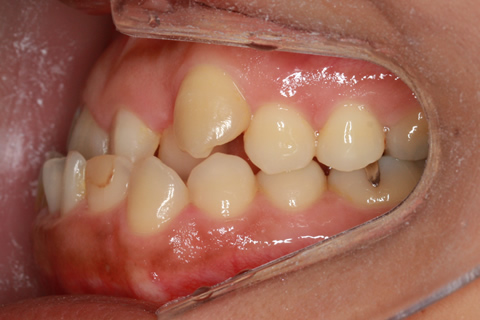

受け口(反対咬合)の症例

症例一覧